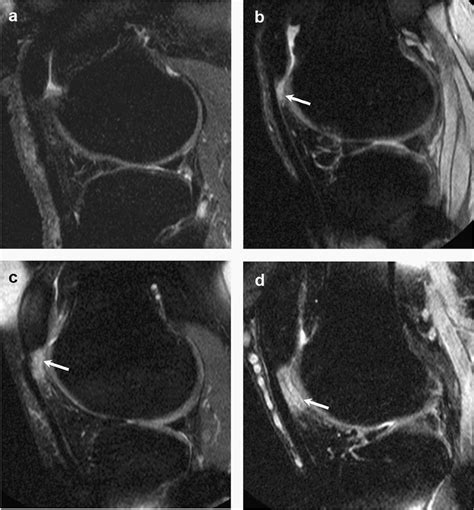

Hoffa’s Syndrome

Hoffa’s Syndrome, also known as Hoffa’s Fat Pad Impingement, occurs when the fat pad becomes inflamed and swollen, often due to repetitive stress or trauma. This condition can cause anterior knee pain, tenderness, and swelling, particularly during activities that involve knee flexion and extension.

Fat Pad Impingement

Impingement of Hoffa’s Fat Pad can occur when the pad becomes trapped or compressed between the patellar tendon and the tibia. This can happen during activities that involve deep knee bending, such as squatting or lunging, and can cause anterior knee pain and stiffness.

Diagnosing conditions related to Hoffa’s Fat Pad typically involves a combination of physical examination, medical history, and imaging tests. Treatment options vary depending on the severity and underlying cause of the condition.

• Imaging tests: X-rays, MRI, or ultrasound may be used to visualize the fat pad and surrounding structures.